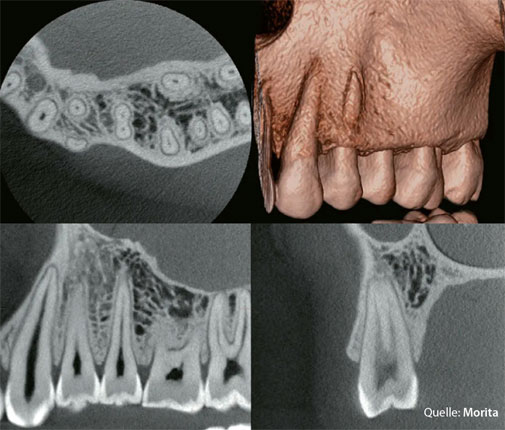

Ein DVT – Digitaler Volumentomograph – ist ein hochmodernes Röntgengerät, das ein dreidimensionales Bild von Zähnen, Kiefer und den umliegenden Strukturen erstellt.

Während herkömmliche zweidimensionale Röntgenaufnahmen nur flache Schatten zeigen, macht das DVT die Situation räumlich sichtbar – bis ins feinste Detail. So lassen sich zusätzliche Wurzelkanäle, Knochendefekte, anatomische Varianten oder verborgene Entzündungen erkennen, die sonst unsichtbar bleiben.

Heute: | Seit Oktober 2025 nutzen wir eines der hochwertigsten DVTs auf dem Dentalmarkt – das Morita Veraview X800 L. Direkt bei uns in der Praxis, digital, KI-gestützt und ohne Umwege. |